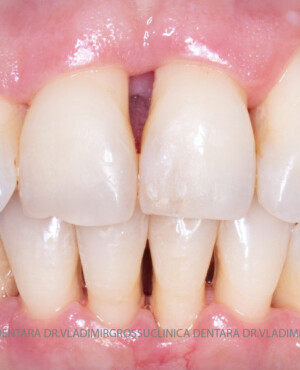

Aditia gingivală este o procedură chirurgicală ce corectează diverse probleme estetice și funcționale, cum ar fi recesiunea gingivală. În implantologia modernă, aditia de țesut moale este utilizată aproape în fiecare intervenție de inserție a implantului dentar pentru a asigura un aspect estetic natural și o bună integrare a implantului în cavitatea bucală.

Adiția osoasă are un rol crucial pentru poziționarea corectă și stabilă a implanturilor dentare. Clinica stomatologică Dr. Grossu din Chișinău promovează o abordare chirurgicală estetică și predictibilă, adaptată fiecărui caz în parte.

Medicii noștri au o vastă experiență atât în chirurgia estetică, cât și în protezarea cu un grad înalt de naturalitate, ceea ce ne permite să gestionăm cu succes și cele mai complexe cazuri.